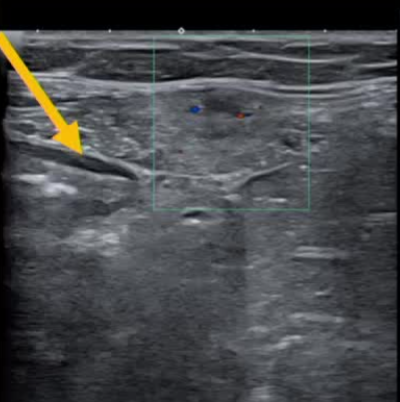

| 腹壁下病变 | MRI引导下 冷冻消融。装有热水的手套在皮肤表面保护皮肤 |

通常需要三根布针

保护措施:几乎所有干预都需要辅助保护措施,其中水分离术(13/16,81.3%)和水分离术与温盐水填充手套的皮肤保护结合(9/16,56.3%)是最常见的保护措施。